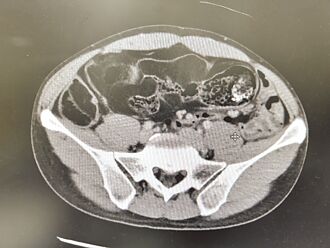

45歲蘇先生長達3天無排便、排氣,因此腹脹無法進食,到急診就醫,竟發現降結腸處有一顆5公分的大腫瘤,導致腸道完全阻塞,醫師懷疑是大腸癌,但因腸阻塞無法施行大腸鏡檢查,與病人討論後,安排手術切除腫瘤、周圍腸段及淋巴節,術後確定為已有淋巴轉移的大腸癌第三期,進一步安排後續化學治療。